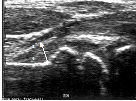

Рис.1. Сонограмма тазобедренного сустава больного С., 6 лет. Утолщение капсулы сустава (стрелка), неоднородность контура фиброзной оболочки, наличие выпота в полости сустава